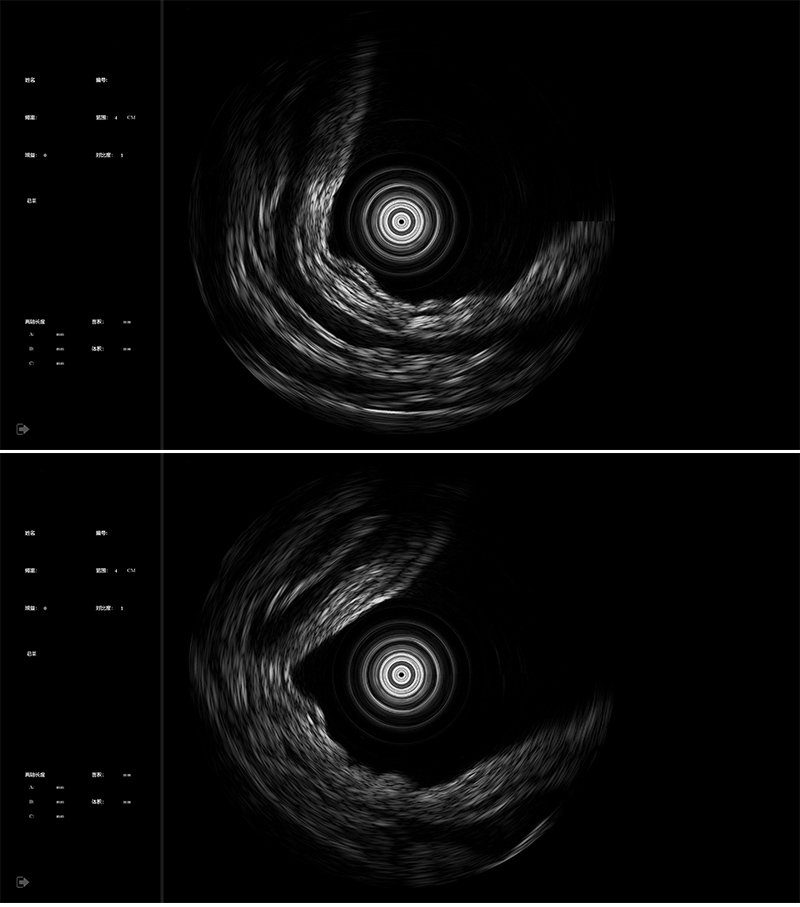

U1000 超声微导管内窥影像设备

360°机械环扫探头

- 多规格尺寸微探头满足临床多样化需求

- 2D机械环扫/3D螺旋扫描可选

- IPX7防水等级,方便清洗消毒彻底